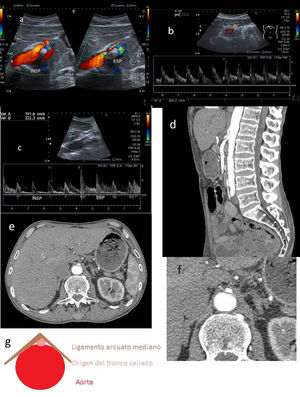

El hallazgo Doppler más relevante es la duplicación de la Vps, respecto a su valor en reposo en la arteria subclavia y la pérdida de la dinámica respiratoria en la vena subclavia en la abducción a 90°. El cese total del flujo arterial y/o venoso en hiperabducción indica oclusión completa2,3. Otro hallazgo es la atenuación del flujo radial con las maniobras de Adson y Allen (fig. 4).

A) Flujo arterial normal en posición neutra de la arteria subclavia. B) Duplicación de la Vps en la arteria subclavia en la abducción a 90° en el síndrome del estrecho torácico (SET). C) Flujo venoso normal en posición neutra de la vena subclavia. D) Pérdida de la dinámica respiratoria en la vena subclavia con las maniobras de abducción en el SET. E) Onda arterial radial normal en posición neutra y atenuada con la maniobra de Adson en el SET. F) Tomografía computarizada con contraste, en proyección coronal, donde se observa compresión de arteria subclavia izquierda en la región costoclavicular.